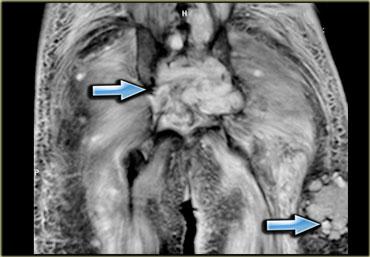

Hình bên trái là một ví dụ, lưu ý các thay đổi viêm ở các cơ lớn vùng mông.

Sau khi ngừng thuốc, đau cơ sẽ biến mất trong khoảng 2 tuần, tuy nhiên MRI vẫn còn cho thấy bất thường cho đến khoảng một tháng sau đó.

Thời điểm tốt nhất để chụp MRI theo dõi là khoảng 6 tuần sau khi ngừng thuốc.

Đây là bệnh nhân cao tuổi có tăng cholesterol máu được chỉ định dùng Lipitor.

Bệnh nhân xuất hiện đau nhức cơ, CPK tăng nhẹ.

Các thay đổi khá tinh tế, chúng ta thấy các ổ tụ dịch quanh mạc cơ, ở rìa ngoài của cơ (ngoại mạc cơ).

Ngoài ra còn có thay đổi da tối thiểu.